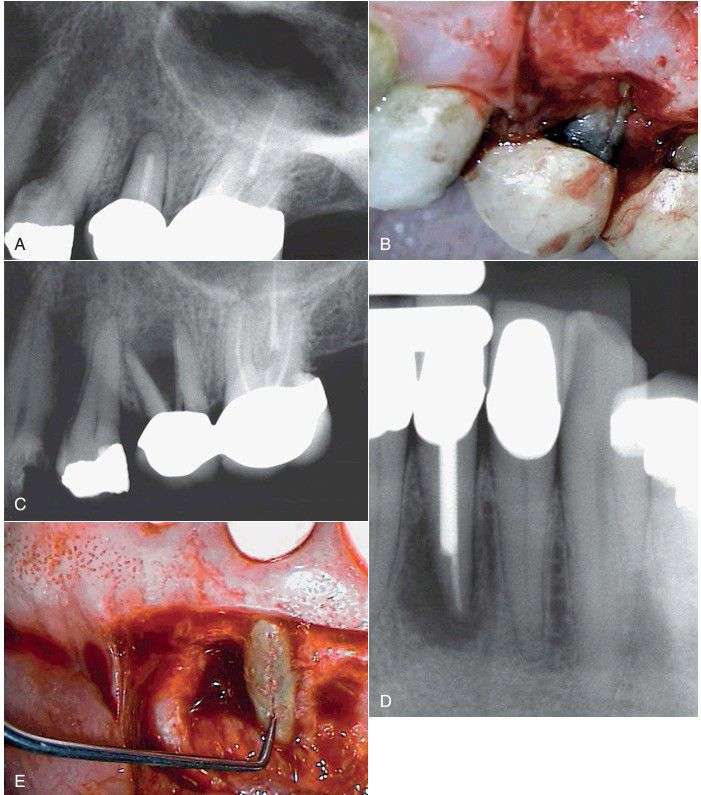

When a vertical root fracture is suspected, sometimes the reflection of a surgical flap over the root may allow better visualization. A, The radiograph here shows no indication of a root fracture. B, However, after surgical exposure, the fracture can be seen. C, Unfortunately, this tooth was never extracted and is observed with a prominent split root 1 year later. D, Similarly, the radiograph of this mandibular anterior tooth shows no indication of a root fracture. E, However, when the root is surgically exposed, the fracture is easily seen.